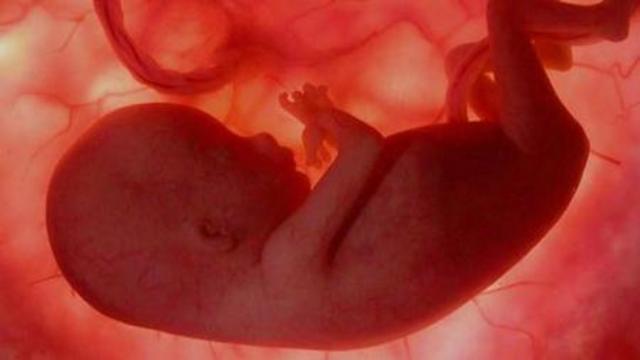

• 32 Semanas de Gestación

32 Semanas de Gestación

El feto orina al rededor de medio lito de orina diario, algunos órganos ya funcionan como la harán despúes del nacimiento como el estomago, intestino y riñones, otros aun no estan preparados como los pulmones y el higado solo en el 8vo mes se completa su crecimiento